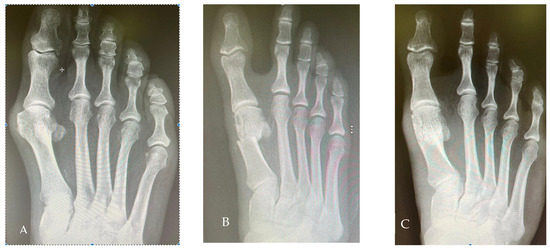

Some examples of pre- to post-operative radiological and clinical changes are shown in Figure 3 and Figure 4.

Figure 3. Radiological views of one case. (A): Preoperative; (B): Two weeks after the operation; (C): Two years after the operation.